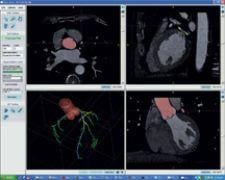

Diagnostic software maker Rcadia Medical Imaging Ltd. recently received a second FDA clearance to market its COR analyzer family of products, which assists in triaging patients for coronary artery disease (CAD).

The new approval includes segmentation of the coronary tree with no human intervention and automatic detection of pathologies in the main coronary arteries. Rcadia’s COR analyzer system uses proprietary image processing algorithms allowing analysis of coronary CTA studies to characterize patients. While improving ED workflow, it can reportedly lead to a more rapid diagnosis, enabling appropriate treatments and avoiding unnecessary delays and invasive tests in patients who do not have coronary artery disease.